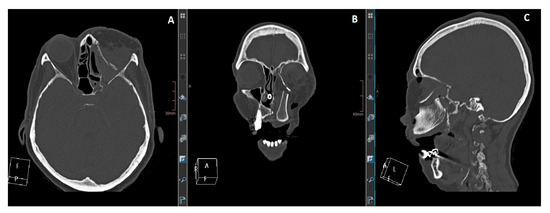

Figure 2. (A): Axial view. (B): coronal view. (C): sagittal view. CT imaging shows the maxilla reconstruction with a DCIA flap and the medial orbital wall and floor with an MFC flap. The reconstruction was delayed for two weeks after the resection to wait for definitive histology.